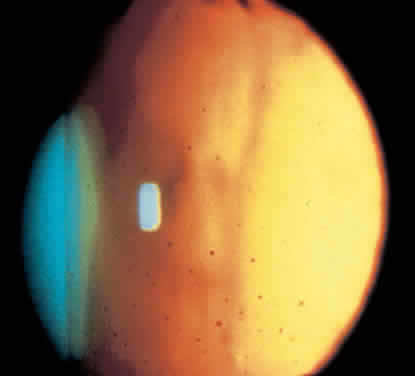

Fig. 7. Retroillumination of an eye with Fuchs' heterochromic iridocyclitis reveals diffuse distribution of keratic precipitates.